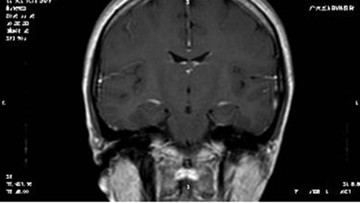

患者影像学资料:

▲术前MRI